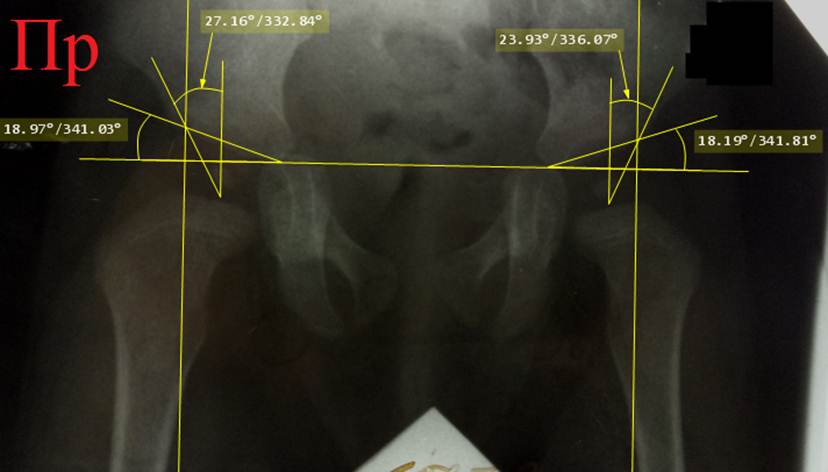

Через

3 месяца, в возрасте 10 месяцев, была сделана контрольная рентгенограмма без

ортеза, на которой все

рентгенометрические параметры значительно выходили за пределы нормы:

ацетабулярные углы превышали 30° с обеих

сторон, ядра окостенения головок бедер

не полностью покрывались крышами вертлужных впадин и большая их часть

находилась кнаружи от линий Омбредана – Перкинса. Ортезирование продолжено

ещё на 4 месяца.

Снимок

в возрасте 1 года 3 месяцев.

Рентгенометрические параметры с натяжками укладываются в норму: ацетабулярные углы превышают норму, но не так

значительно, в пределах 2-3 градусов. Угол Виберга равен не больше 2-3 градусов

с обеих сторон (не начерчен), но все же он больше нуля. Ядра окостенения головок бедер лежат не

полностью кнутри от линий Омбредана – Перкинса. Ортезирование шиной БелНИИТО прекращено.

Назначено применение шины Виленского⃰

сроком на полгода. На

контрольном снимке в возрасте 5 лет все рентгенометрические показатели были в

норме, углы Виберга с обеих сторон 25°.